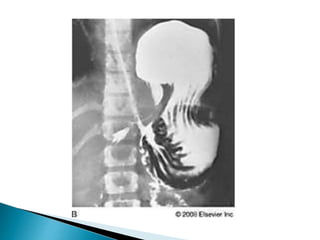

"Corkscrew" duodenum in malrotation with a midgut volvulus

"Corkscrew" duodenum in malrotation

with a midgut volvulus

"Corkscrew" duodenum inmalrotation with a midgut volvulus "Corkscrew" duodenum in malrotation with a midgut volvulus